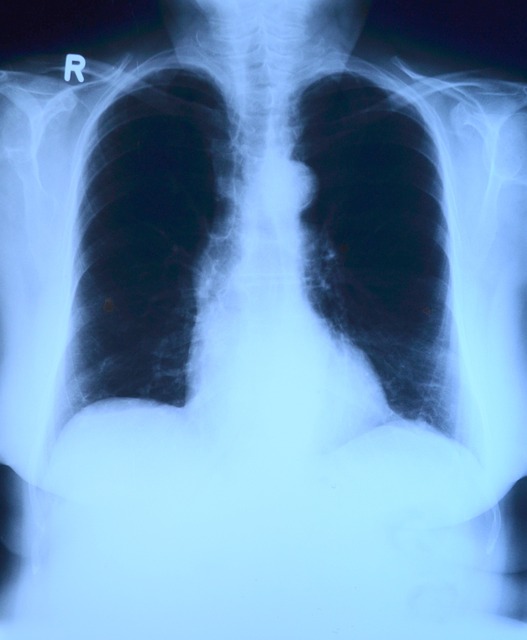

폐렴에 걸리면 폐에 염증이 생겨서 발생하는 폐 증상과 신체 전반에 걸친 전신적인 증상이 나타납니다. 보통은 기침, 가래, 호흡곤란 등의 증상이 나타나지만 폐를 둘러싸고 있는 흉막까지 염증이 침범한 경우에는 숨쉴 때 통증이나 구토, 설사의 증상도 발생할 수 있습니다. 또한 두통과 피로감, 근육통 등의 전신 질환이 동반되기도 합니다.